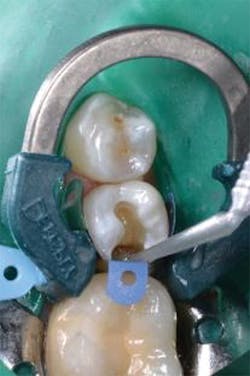

Figure 4: Palodent Plus Sectional Matrix System placed. Prime&Bond Elect Universal Adhesive is applied to the entire preparation and agitated for 20 seconds. After air drying the adhesive for five seconds, the adhesive is light cured for 10 seconds.

Figure 5: To seal the proximal box, SureFil SDR flow+ bulk-fill flowable composite (Universal Shade) is placed in up to a 4 mm increment. Because of its low viscosity, SureFil SDR flow+ provides excellent adaptation to irregular cavity geometry.